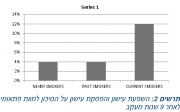

| 15:14, 10 במרץ 2016 | Smoking cessation3.jpg (קובץ) |  |

226 קילו־בייטים | Motyk | 1 | |

| 14:55, 10 במרץ 2016 | Smoking cessation2.jpg (קובץ) |  |

72 קילו־בייטים | Motyk | 1 | |

| 13:54, 10 במרץ 2016 | Smoking cessation1.jpg (קובץ) |  |

111 קילו־בייטים | Motyk | 1 | |